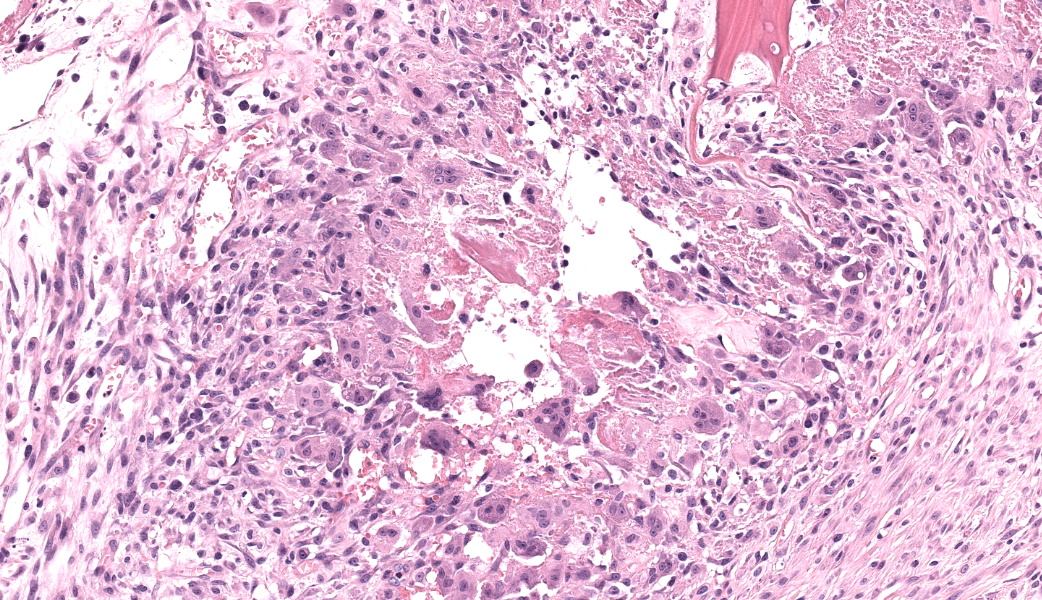

Femoral head: Affecting approximately 30-50% of the epiphysis from the subchondral aspect of the articular cartilage to the physis, there is a focally extensive area of osteonecrosis characterized by bony trabeculae which are irregular and brightly eosinophilic with loss of differential staining. There is loss of both osteocytes within lacunae and osteoblasts lining trabeculae in this region. Along the margins of the necrotic area, multiple bone trabeculae are fragmented and/or have scalloped margins with osteoclasts in Howship’s lacunae (osteolysis). The intertrabecular spaces within and at the periphery of the necrotic area contain variably amounts of amorphous eosinophilic matrix (fibrin), occasional neutrophils and macrophages and/or loosely arranged myxomatous to collagenous matrix with variable numbers of plump spindle cells and capillaries (fibroplasia). Occasionally, there are also finer, irregular trabeculae of paler staining or partially mineralized bone (woven bone). Adjacent viable trabeculae are lined by numerous active osteoblasts (remodeling) and are sometimes laced with wavy basophilic lines (resting / resorption lines). The articular cartilage is fragmented (likely artefact).Contributor's Morphologic Diagnoses:

The contributor of this case gives an excellent overview of this condition.Most of conference discussion was centered on pathogenesis and key histologic features of this condition. This disease can be, as stated by the contributor, either hereditary or secondary to trauma or other ischemic event.1,3,4,5,6 The hereditary form is most often seen in young, small breed dogs, such as terriers, dachshunds, pugs, Chihuahuas, and toy poodles. When looking at this case, there are a few histologic clues that can assist in determining the age of this animal, which can help with reaching the correct diagnosis. These include the presence of discontinuous physeal cartilage and the horizontal orientation of the bony spicules deep to the physis. In dogs, physes typically close around 10 months of age. Physis closure in Legg-Calves-Perthes disease (LCPD) is typically delayed secondary to ischemia of the physeal cartilage and the subchondral bone, which can result in a malformed or improperly angled femoral head.1 Additionally, in young animals, the bony spicules that extend into the metaphysis from the developing stages of the growth plate are oriented vertically (perpendicular) to the growth plate to facilitate the elongation of the bone. In older animals that have closed physes, the bone below the growth plate becomes oriented horizontally (parallel) to the growth plate, effectively “capping” it to facilitate closure of the physes. In this case, the bone has become horizontally oriented below the growth plate, indicating that this animal should have closed physes at this stage, but the presence of and discontinuity of the lingering growth plate indicate that this young animal is likely experiencing delayed physeal closure.

Differentiating necrotic bone from normal bone can be challenging, but one of the key features to look for is the loss of osteocytes from lacunae.5 Osteocytes either become pyknotic and hypereosinophilic or disappear entirely, and you can best convince yourself this is a real change (and not just a staining artifact) by comparing an area of suspected necrosis to an area of less affected or normal bone where the osteocytes will still be in their lacunae and have a nice, basophilic nucleus. Another useful way to determine osteonecrosis is to assess the bone marrow. In necrotic bone, there is usually histologic loss of marrow elements secondary to ischemia, which will manifest as a loss of differential staining with retention of architecture within the marrow.